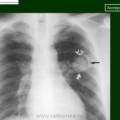

Аспергиллёма легких - находящийся в полости легкого или в бронхоэктазе подвижный конгломерат переплетенных аспергиллезных гиф, покрытый фибрином, слизью и клеточными элементами (по степени затемнения соответствует жидкости), располагающийся внутри овальной или сферической капсулы, отделяясь от нее воздушной прослойкой, с утолщением плевры.